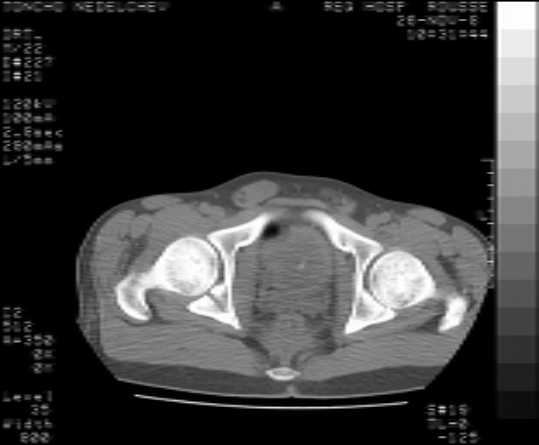

Here are some more axial images. What is your opinion as for the timing of the operative treatment?

The details of the fracture are not so clear from the images sent...would you be able to send along an AP and Judet images as well as some additional axial images above and below the joint?

Without complete CT images and/or oblique radiographs, it's difficult to answer your question definitively, but it appears that there may not be a posterior wall fracture that requires a posterior approach. A successful reduction through an ilio-inguinal approach will have a faster recovery, and not risk SGN injury or heterotopic ossification.